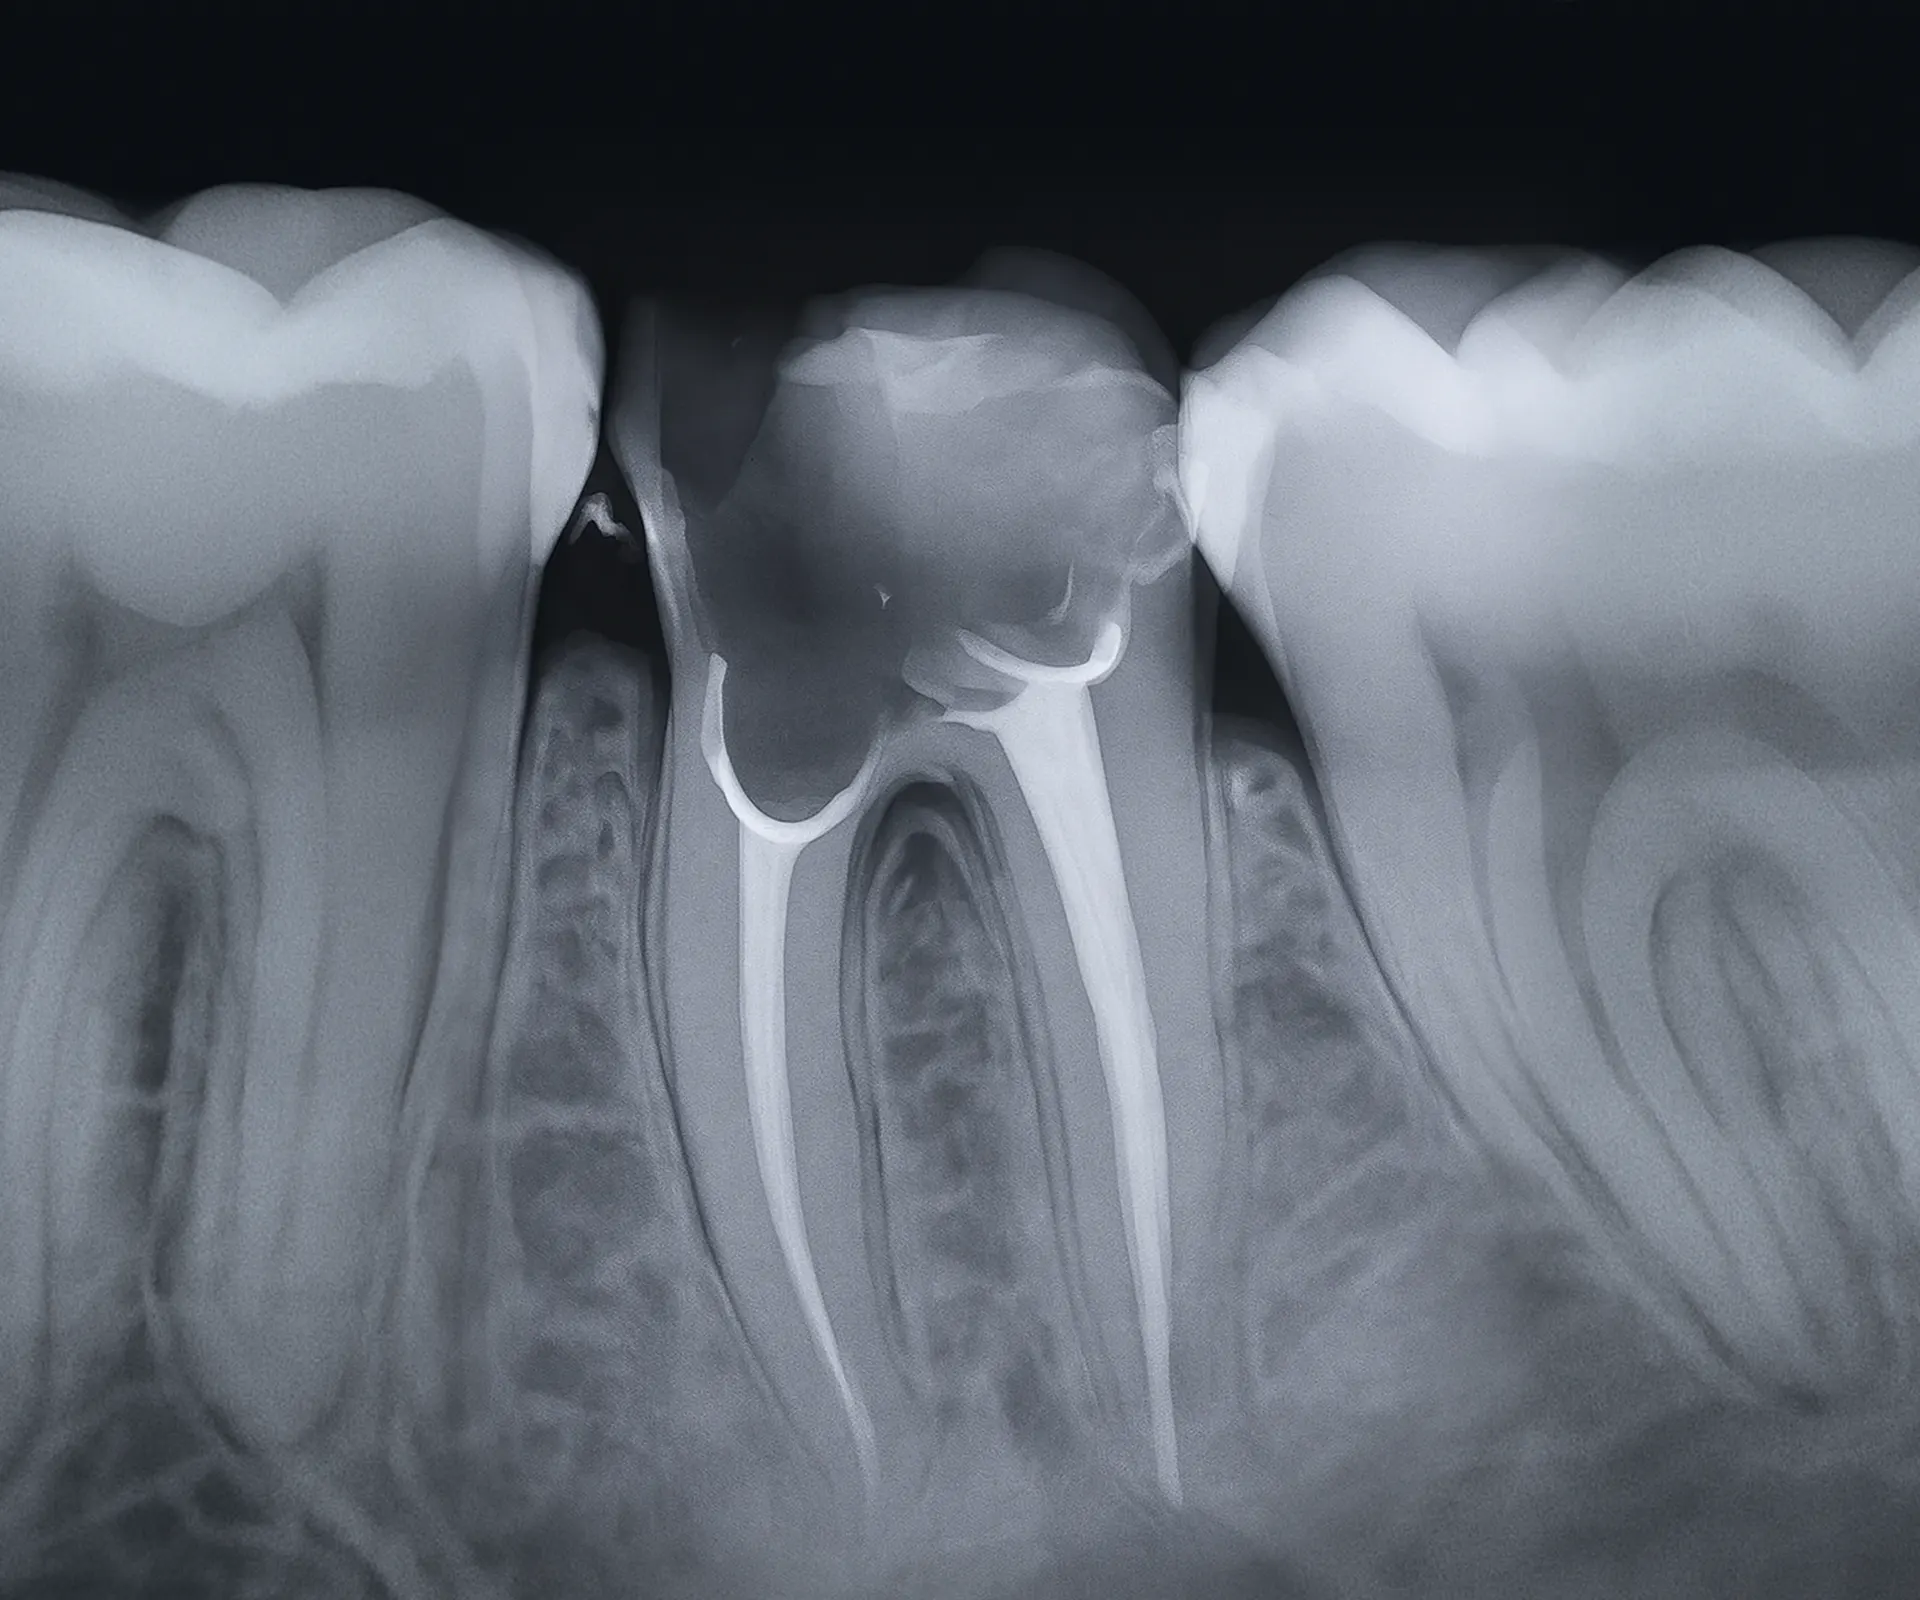

Intraoralna snimka zubi – preciznost u fokusu

Intraoralna rendgenska snimka omogućuje izuzetno detaljan prikaz pojedinačnih zuba ili manjih regija usne šupljine. Idealna je za otkrivanje karijesa, problema s korijenom zuba, provjeru ispuna i statusa oko zubnog živca. Zahvaljujući digitalnoj tehnologiji, rezultati su trenutno dostupni i spremni za analizu.